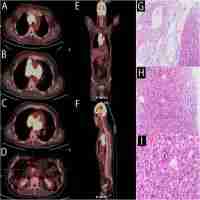

| Description | Patients with relapsed/refractory (R/R) transformed diffused large B cell lymphoma (tDLBCL) have a poor prognosis and a low survival rate. In addition, no standard therapy has yet been established for R/R tDLBCL. Herein we presented a single case of a patient with R/R tDLBCL who was successfully treated with sintilimab and chidamide. The patient was a 71-year-old man with pulmonary mucosa-associated lymphoid tissue lymphoma. He did not receive any treatment until tDLBCL was confirmed 2 years later. The tDLBCL was primary refractory to R2-CHOP, R2-MTX, and Gemox regimens. However, the patient achieved sustained complete remission after the combination therapy of sintilimab and chidamide. To the best of our knowledge, this is the first report of sintilimab combined with chidamide for the treatment of R/R tDLBCL, which opens up new therapeutic possibilities for this new combination therapy in future prospective clinical trials. |

| Abstract | Relapsed/refractory (R/R) transformed diffused large B cell lymphoma (tDLBCL) has a poor prognosis, studies about new therapies for tDLBCL are scarce. PD-1 antibody and histone deacetylase inhibitor both have anti-lymphoma effects but the combination of these two therapies hasn’t been explored in DLBCL. Here, we present a successful combination therapy of sintilimab and chidamide for R/R tDLBCL. The patient was a 71-year-old man with pulmonary mucosa-associated lymphoid tissue lymphoma. He didn’t receive any treatment until transformed DLBCL was confirmed 2 years later. The tDLBCL was primary refractory to R2-CHOP, R2-MTX, and Gemox regimens. However, he achieved sustained complete remission after the combination therapy of sintilimab and chidamide. According to our knowledge, this is the first report of sintilimab combined with chidamide for treatment of R/R tDLBCL, which opens up new therapeutic possibilities of this new combination therapy in future prospective clinical trials. |